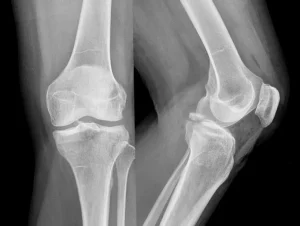

1. Kapalı Fraktür

Kapalı fraktür, kemikte bir kırılma olmasına rağmen cildin bütünlüğünün bozulmadığı durumlardır. Yani kemik kırılır ancak deri kesilmez ve dışarıya çıkmaz.

4. İzole Fraktür

Kemik yalnızca tek bir bölgeden kırılır ve etraftaki diğer dokularda ciddi bir hasar olmaz. Tedavi genellikle daha kolaydır.